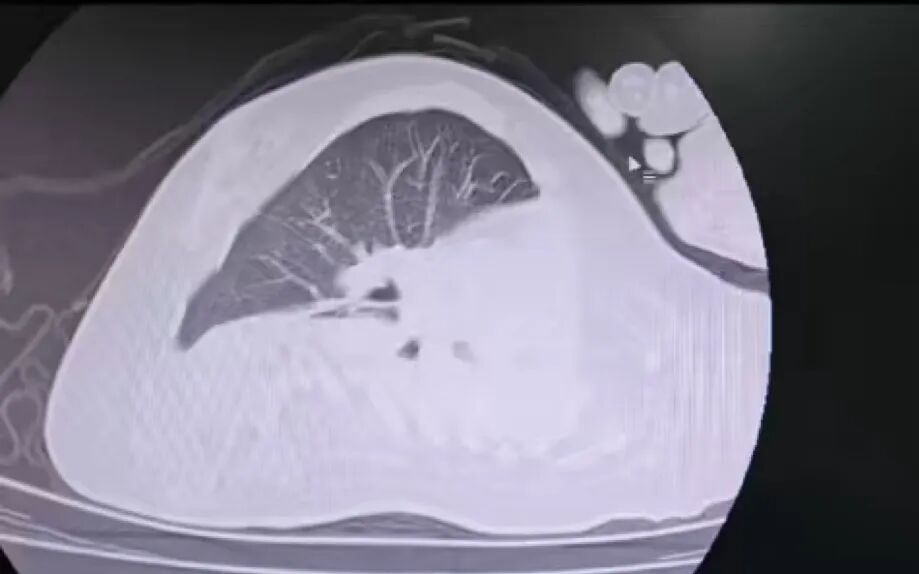

治療前

該患兒因患脊髓性肌萎縮癥長期臥床,呼吸肌已嚴(yán)重?zé)o力,自主呼吸微弱且?guī)缀鯁适Э人耘盘的芰?,此次并發(fā)支氣管肺炎后,肺部感染迅速加重,生命已然懸于一線。更棘手的是,嚴(yán)重的脊柱側(cè)彎使患兒胸廓畸形、氣道解剖結(jié)構(gòu)明顯移位,常規(guī)纖支鏡進(jìn)鏡路徑完全失效,扭曲狹窄的氣道如同縱橫交錯的“迷宮”,每一步操作都必須精準(zhǔn)到毫米級別。

體位擺放則成為另一道“攔路虎”,既要滿足纖支鏡操作需求,又要避免側(cè)彎脊柱受壓、防止肌萎縮引發(fā)關(guān)節(jié)脫位,每個角度都得反復(fù)測算。同時,還需直面層層疊加的術(shù)中危機(jī):因患兒呼吸肌功能幾乎喪失,纖支鏡占用狹窄氣道空間后,缺氧、二氧化碳潴留及急性呼吸衰竭、心跳驟停風(fēng)險陡增;灌洗過程中若液體殘留將加重肺部感染,而患兒免疫力低下,導(dǎo)致敗血癥的風(fēng)險顯著升高。